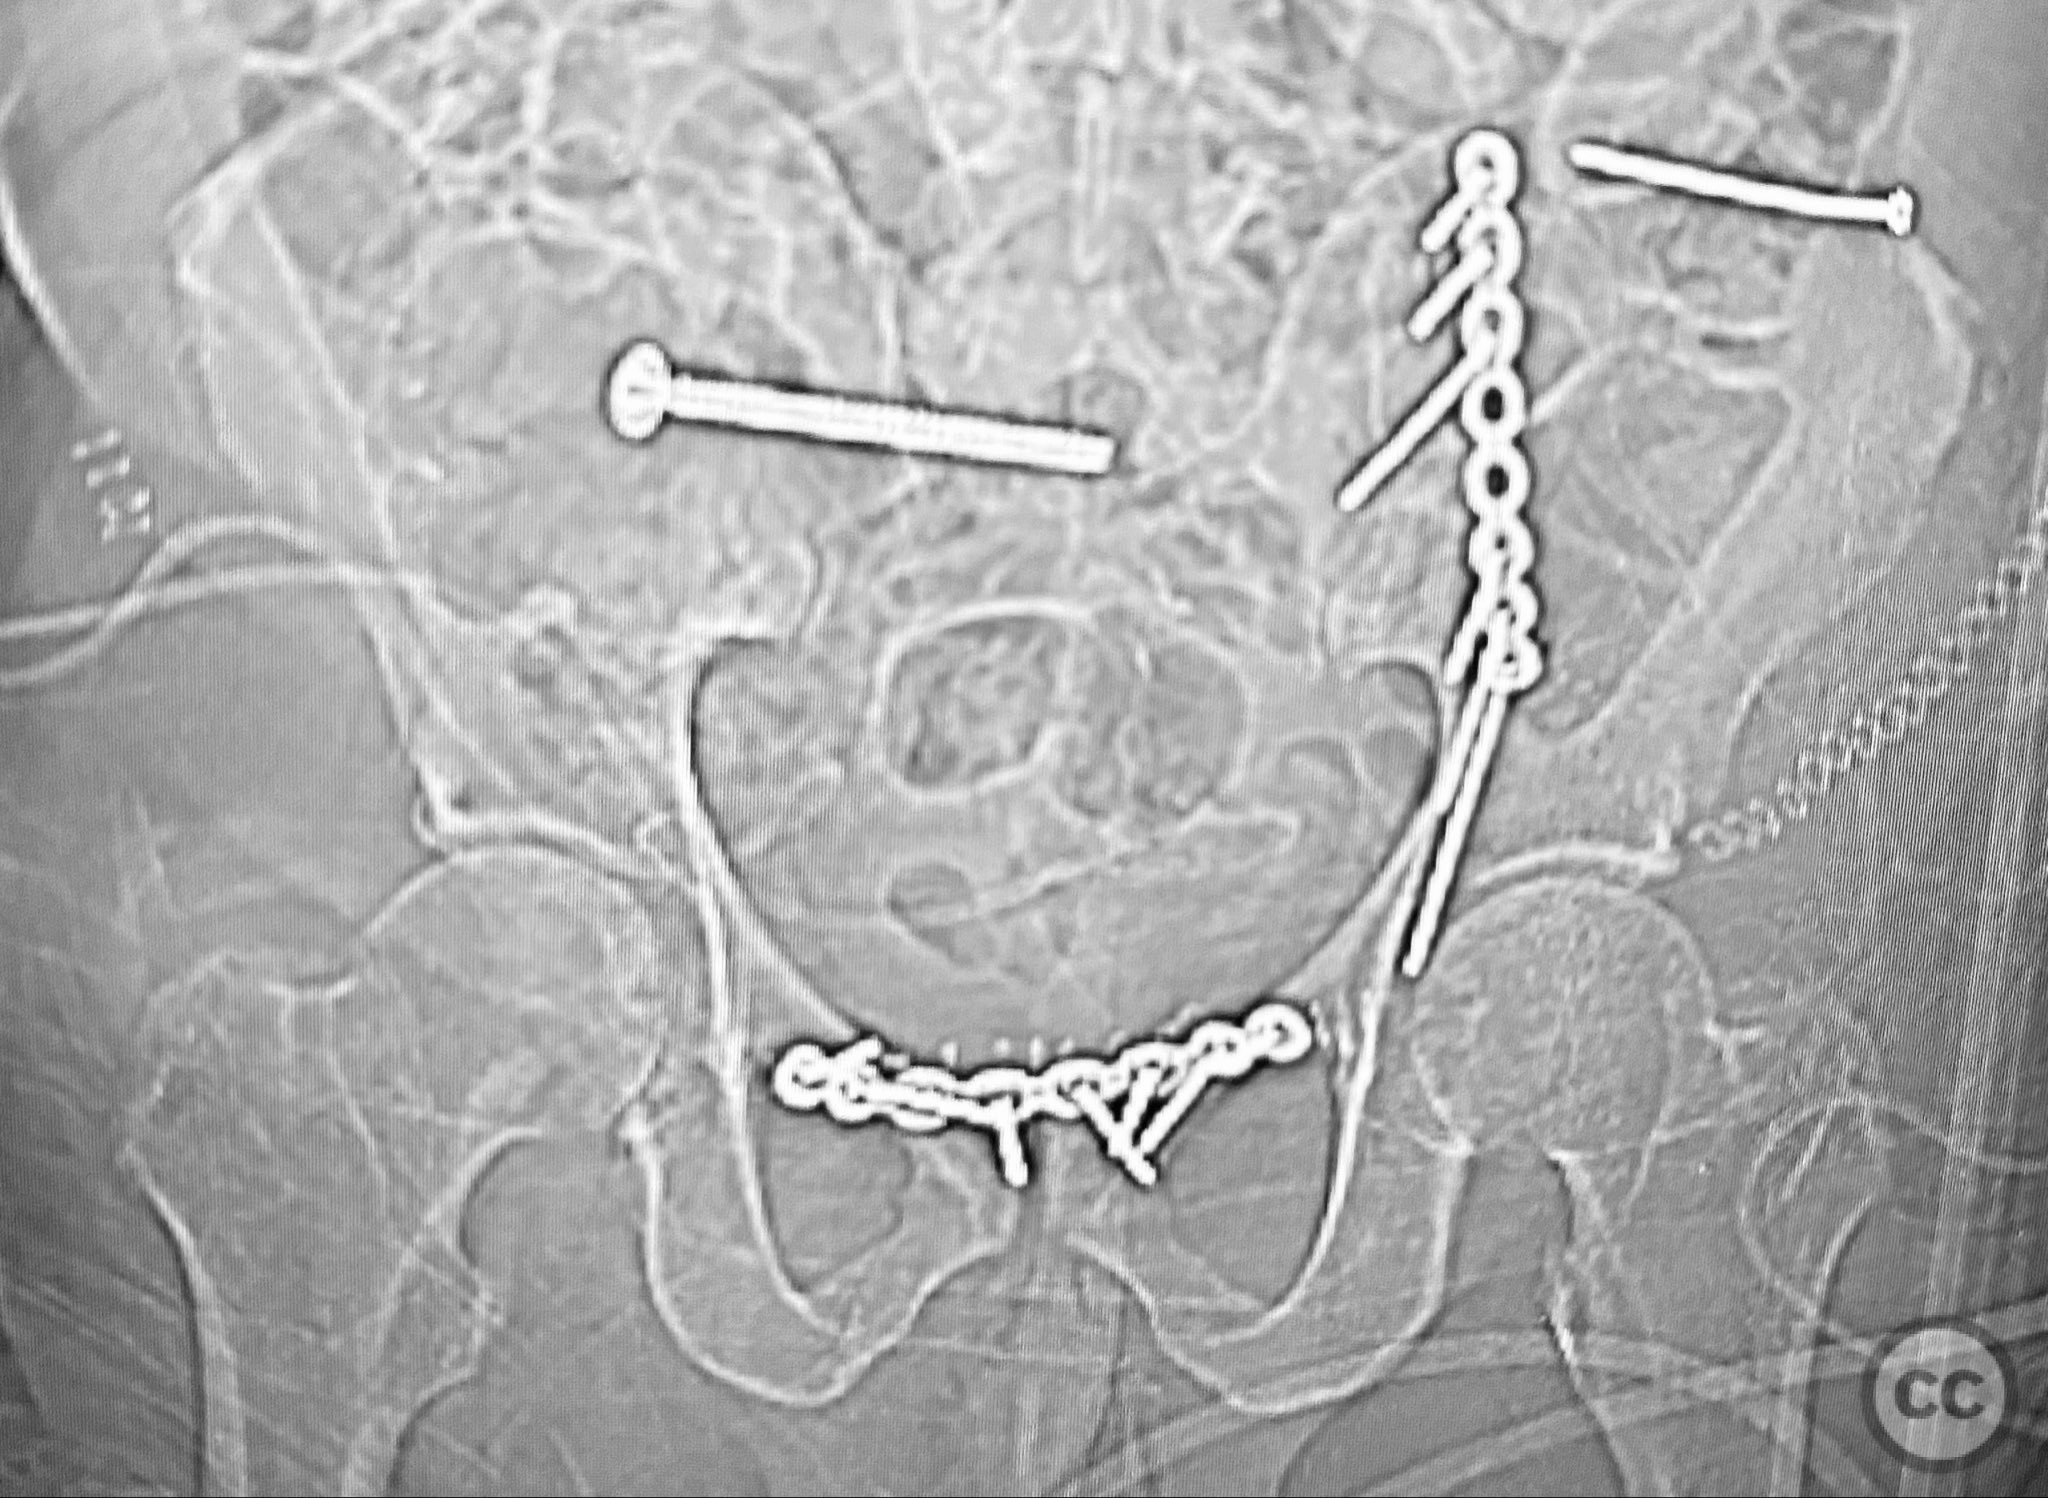

Complete Iliac Fracture with Symphysis Pubis Disruption and Contralateral Incomplete SI/Iliac Fracture

Clinical Details

Clinical and radiological findings:  A patient sustained a high-energy pelvic ring injury characterized by a complete left iliac fracture extending from the iliac crest to the greater sciatic notch, associated with a complete disruption of the symphysis pubis (SP). Additionally, there was a less displaced, incomplete right sacroiliac (SI)/iliac fracture. The injury pattern is consistent with an AO/OTA 61-B2.3 (lateral compression type II) pelvic ring injury. No neurovascular compromise or significant soft tissue injury was reported.

Accurate anatomical reduction was achieved at both the iliac crest and pelvic brim using direct clamp application. Stable fixation was performed at each site according to biomechanical principles, utilizing plates and/or screws as indicated by fragment size and displacement. For closure of the symphysis pubis, interrupted 2-0 Vicryl pop-off sutures on a non-cutting needle were used for the midline portion, with additional 0 Vicryl sutures for reinforcement at the tendon insertion area.

Orthopaedic implants used:   Pelvic reconstruction plate(s), cortical screws, 2-0 Vicryl sutures, 0 Vicryl sutures